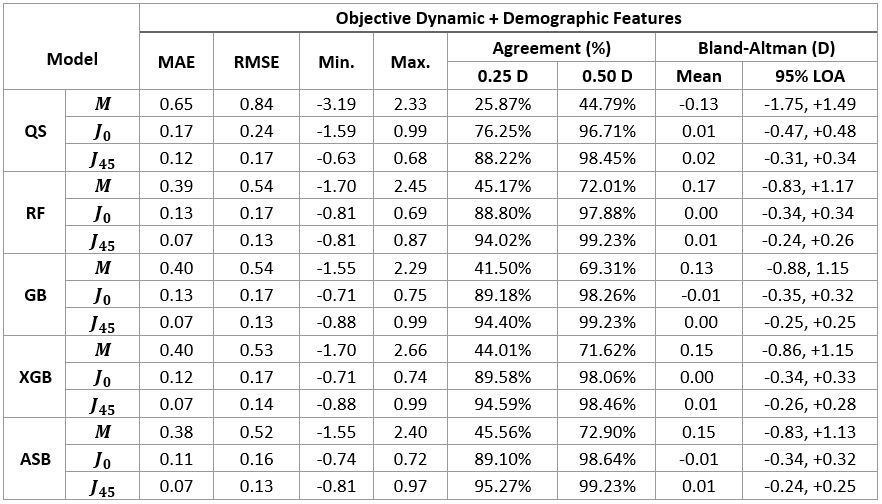

PurposeUncorrected Refractive Errors (UREs) is a reversible condition that can be treated with appropriate eyeglasses. UREs affect over 1 billion people globally, with 90% of this population living in low-and-middle-income countries where vision exams can be highly inaccessible due to a shortage of experienced eyecare professionals. This work aims to assess if a machine learning (ML) approach, when applied to data obtained with an affordable handheld autorefractor, could increase access to clinical-quality subjective refraction (SR) when operated by non-experts. MethodsData used for this analysis was obtained from a clinical study performed at Aravind Eye Hospital in Madurai, India, using a low-cost portable wavefront aberrometer, an early prototype of the QuickSee (QS) (PlenOptika, Inc., USA). A total of 669 participants were enrolled with ages ranging between 15 and 70 years (35.2 ± 13.7) and spherical equivalent error between -6.0 D and 3.5 D (-0.7 ± 1.67 D). Four ML regressor models were trained and tested for each power vector M, J0 and J45: random forest (RF), gradient boosting (GB), extreme gradient boosting (XGB), and a custom assembly model (ASB) that averages the predictions of RF, GB, and XGB. Algorithms were trained on a dataset of 1,244 samples using as input features: age, gender, Zernike coefficients up to 5th order, and measurement quality related metrics provided by the autorefractor. A smaller subset of 518 unseen samples was used to test the agreement of the predictions against SR using Bland-Altman analysis, overall prediction error in terms of mean absolute error (MAE) and root mean squared error (RMSE), and the percentage of agreement for 0.25 D and 0.5 D thresholds. ResultsAll models improved the agreement with SR compared to the baseline autorefraction, but ASB obtained the best results (Table 1). Bland-Altman analysis showed a decrease in the 95% limits of agreement of ±0.63 D, ±0.14 D, and ±0.08 D for M, J0 and J45, respectively. The wavefront-aberrometry related variables had the biggest impact on the prediction, while demographic and measurement quality-related features showed a heterogeneous but consistent predictive value. ConclusionsThese results suggest that ML is effective for improving precision in predicting patient’s SR from objective measurements taken with a low-cost portable device. |